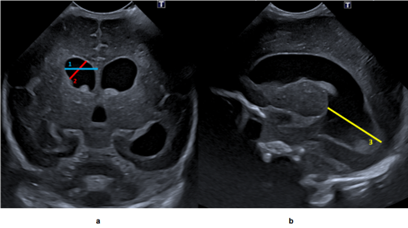

Figuur: Verwijding van de hersenkamers en verschillende metingen vanaf de voorkant (a) en de zijkant (b).